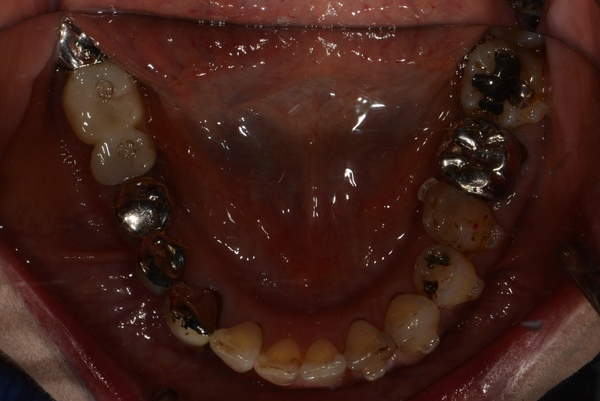

〇ご相談内容:歯並びがよくない〇矯正の種類:マウスピース型矯正「インビザライン」〇治療期間:39週間〇治療費用:44万円(税込)